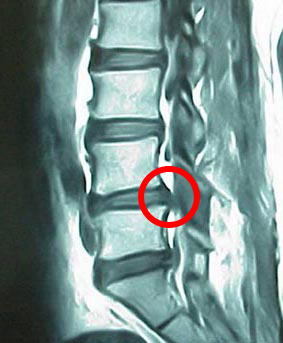

*google画像より引用

上の写真が椎間板ヘルニアの写真で、右の写真は正常な腰椎の写真です。

これを見るといかにも左の写真は痛そうに見えます。しかし、、、